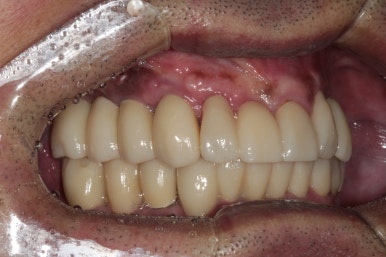

이루 말할 것 없이 깔끔하게 정리된 교합면 사진입니다.

사실 각 어금니마다 1개씩 임플란트가 더 식립되는 것이 28개의 치아를 재건하는데 필수적이나, 남성임에도 불구하고 턱이 아주 크진 않으셨기에 24개의 크라운만으로도 충분히 만족스러운 결과를 얻을 수 있었습니다.!!

다시봐도 지르코니아 크라운의 색상은 너무나 자연스러운 것 같아요... 상당히 완성도 있게 마무리 되었던 케이스였습니다. 개원 초기부터 믿고 잘 따라와주심에 감사드립니다 :)